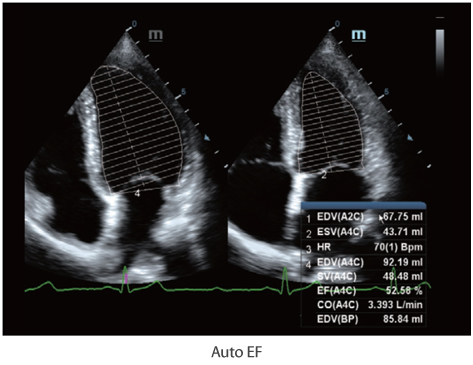

Auto EF is an intelligent way to analyze 2D echo clips to automatically recognize diastole & systole frames and output a series of measurements to evaluate left ventricle function for more productivity, such as EDV/ESV/EF.